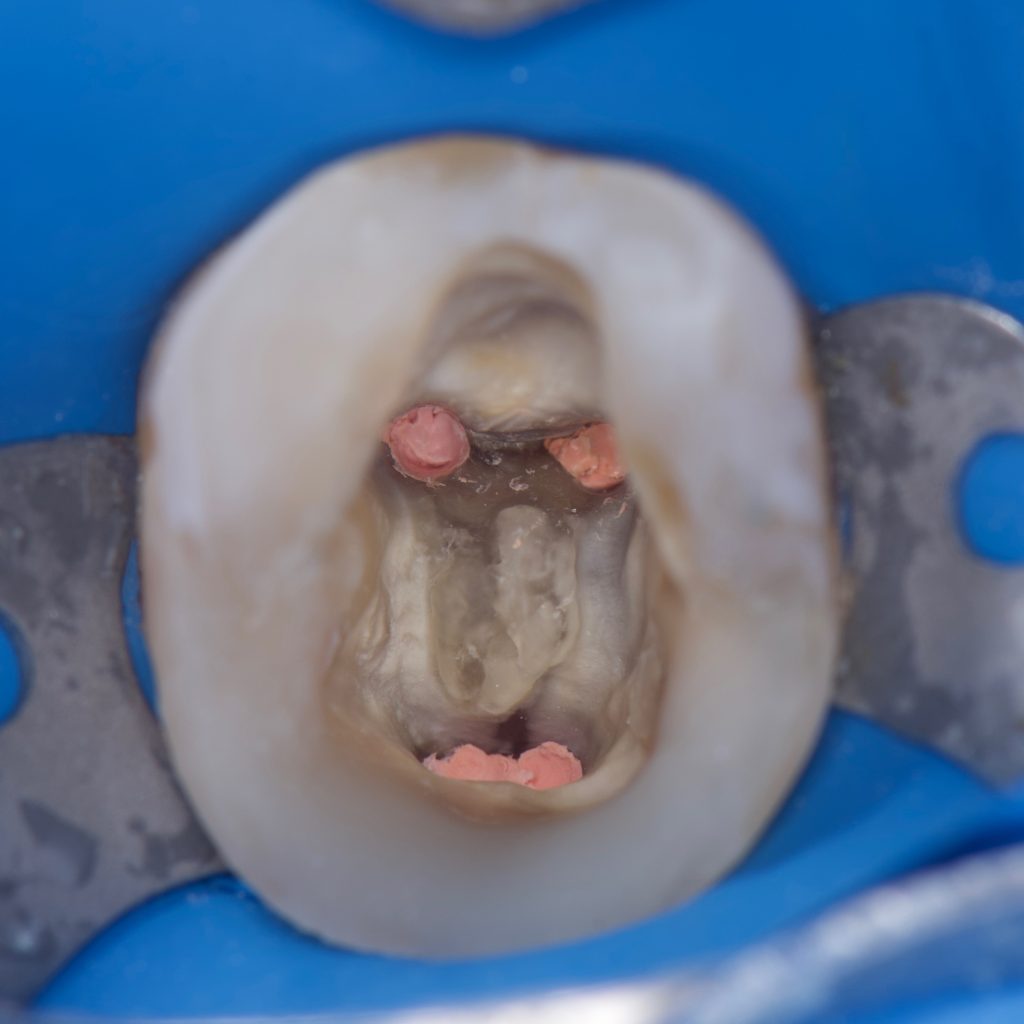

– Treatment began with removing the old amalgam filling and cleaning the tooth from the remaining caries and excess Gutta percha

– Deep margin elevation done with gold standard Bond and Ap-x composite